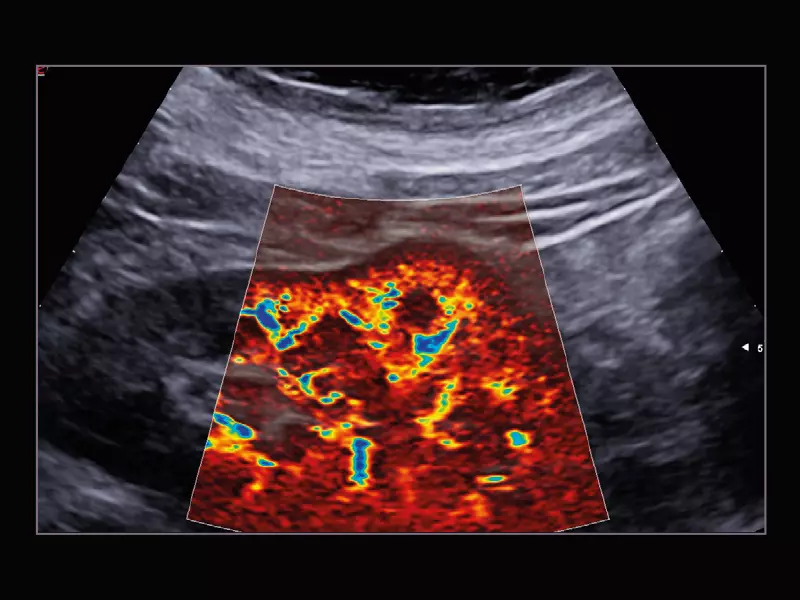

MyLab™Sigma - Kidney perfusion with high sensitivity Color Doppler mode

MyLab™Sigma - Kidney perfusion with high sensitivity Color Doppler mode